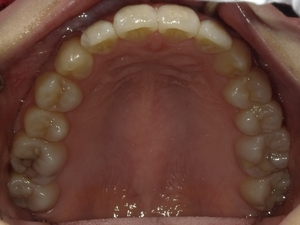

ガタガタとした歯並びや八重歯(叢生)CASE68